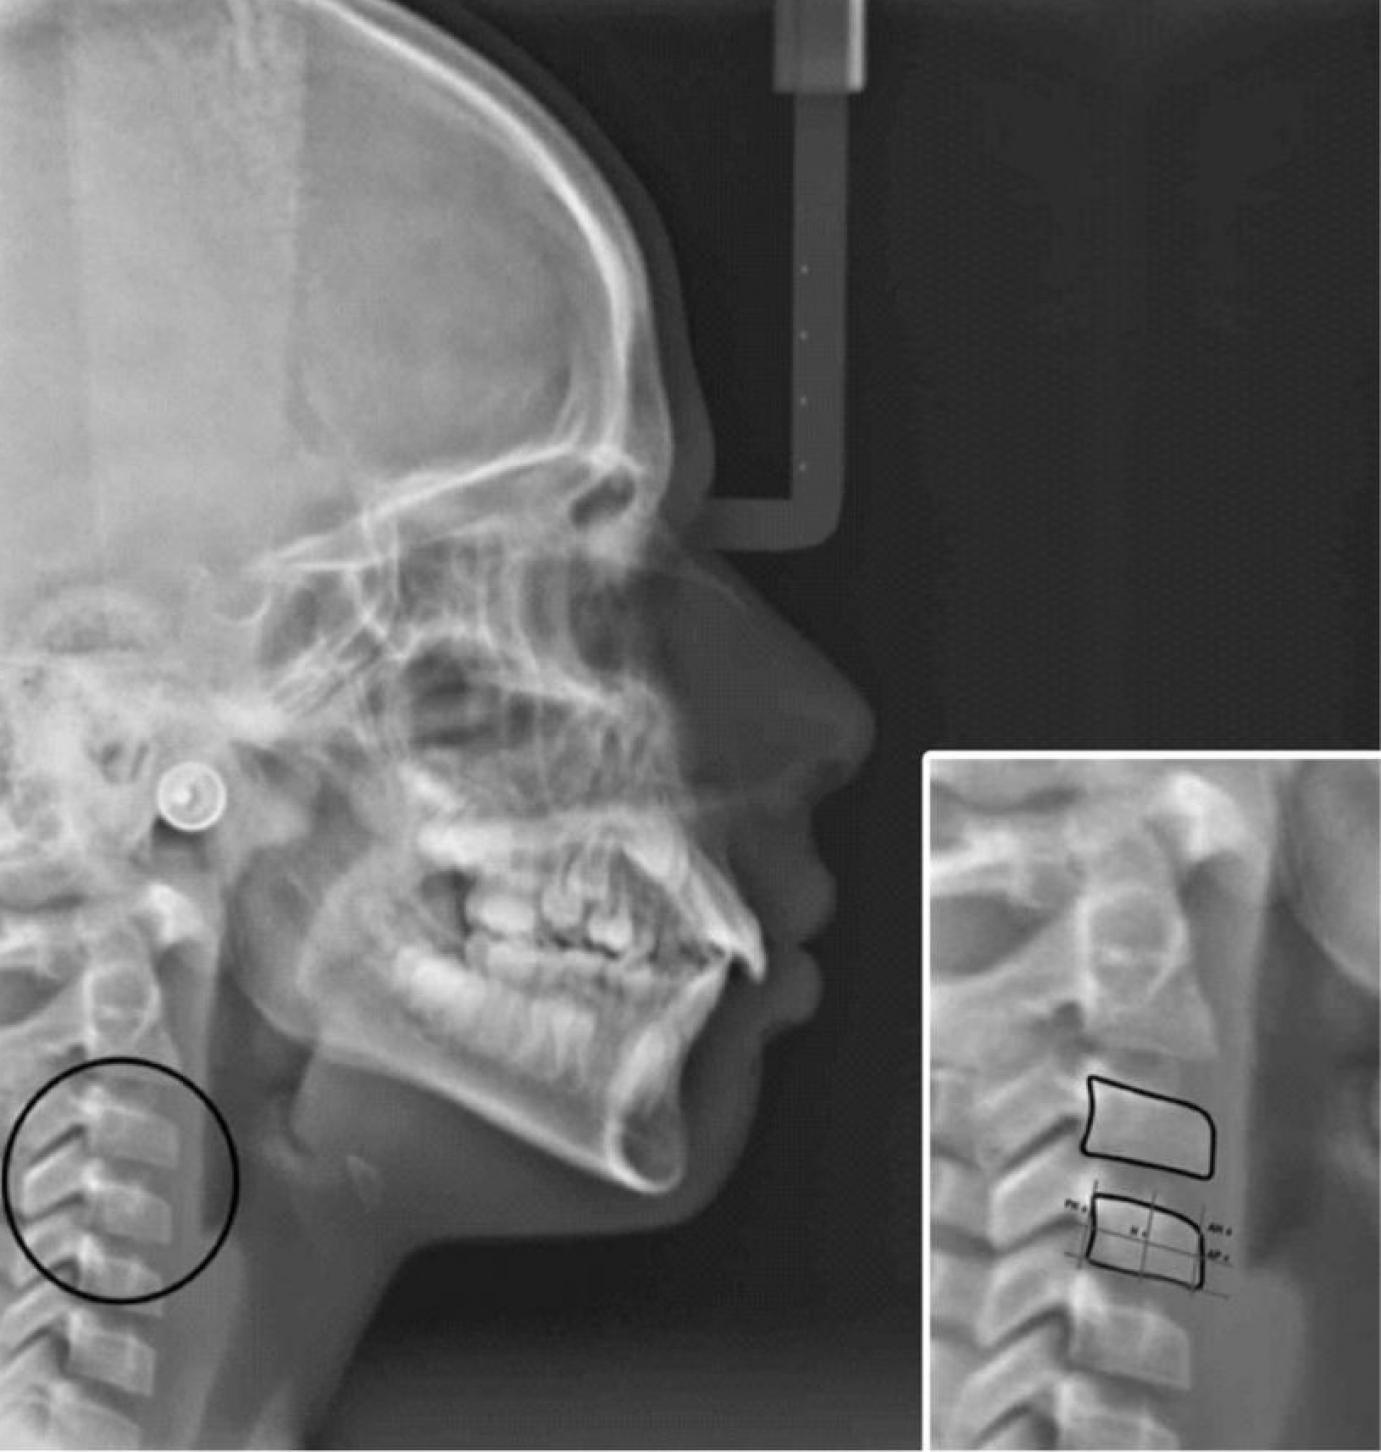

Csontérettség vizsgálata

Azokban az esetekben, amikor az állcsontok hibás mérete vagy pozíciója felmerül a fogszabályozó kezelés megkezdésekor, célszerű csontérettség vizsgálatot végezni. Szerencsére speciális beavatkozást nem igényel a biológiai kor meghatározása. A teleröntgen felvételen a csigolyák formájából lehet következtetni arra, hogy az állcsontokban mennyi növekedési potenciál maradt még, amit felhasználhatunk a fogszabályozó kezelés közben.